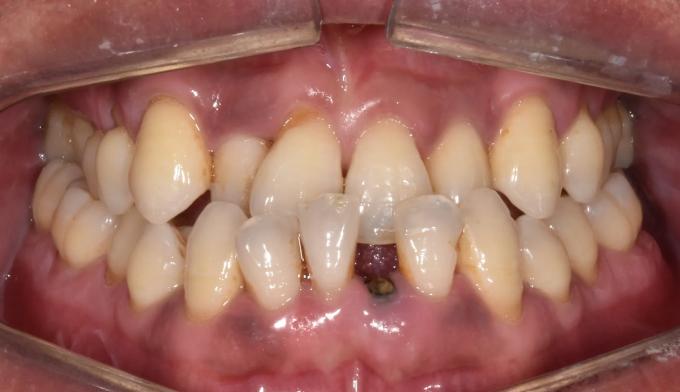

치아결손

10대

2025.02.10